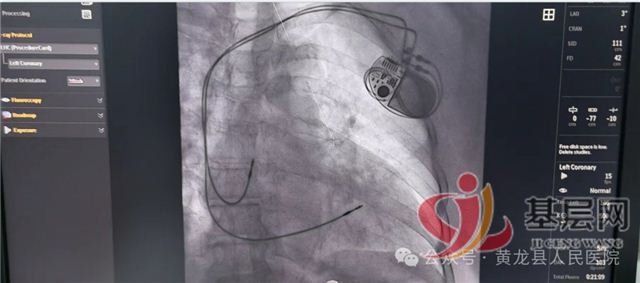

患者高某,女,68岁,以“发作性胸闷、气短6年,加重3天”入院,入院诊断:冠状动脉粥样硬化性心脏病 稳定型心绞痛,造影检查提示一支血管严重狭窄,在介入手术室顺利植入支架1枚。

患者袁某,女,77岁,以“间断胸闷、气短40年,加重10天”入院,入院诊断:冠状动脉粥样硬化性心脏病 不稳定型心绞痛,造影检查提示:一支血管严重狭窄,在介入手术室顺利植入支架2枚、药物球囊1枚。

患者胡某,女,57岁,以“胸痛3小时”就诊于急诊科,诊断胸痛待查,经急诊冠脉造影检查排除心源性胸痛。

飞利浦数字减影血管造影系统

Azurion 7M20